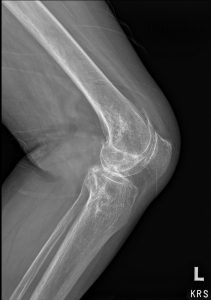

Fig. 2 Lateral view of the knee

Fig. 4 Annotated xray of the knee showing signs of degenerative joint disease (DJD) and regions of sclerosis.